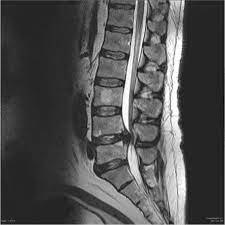

MRI

img01

Mri MAGNETOM Aera 1.5T Tesla

• Comfortable & Open

Wide 70 cm open design, quieter scans, and mostly feet-first exams to reduce anxiety and claustrophobia.

• Fast & Smooth Experience

AI-assisted technology for shorter scan time and higher resolution.

• Clear & Accurate Results

High-resolution images for brain, spine, joints, heart, abdomen, breast, and pediatric exams.

• Ideal for All Patients

Low table for easy access, supports up to 250 kg, and designed for children, elderly, and nervous patients.

• Safe With Implants & Movement

Advanced motion and metal-artifact reduction for clean images even if you move or have implants.

• Eco-Friendly & Reliable

Zero helium boil-off for safer, eco-conscious performance.

• Exceptional image quality

With Tim 4G Technology